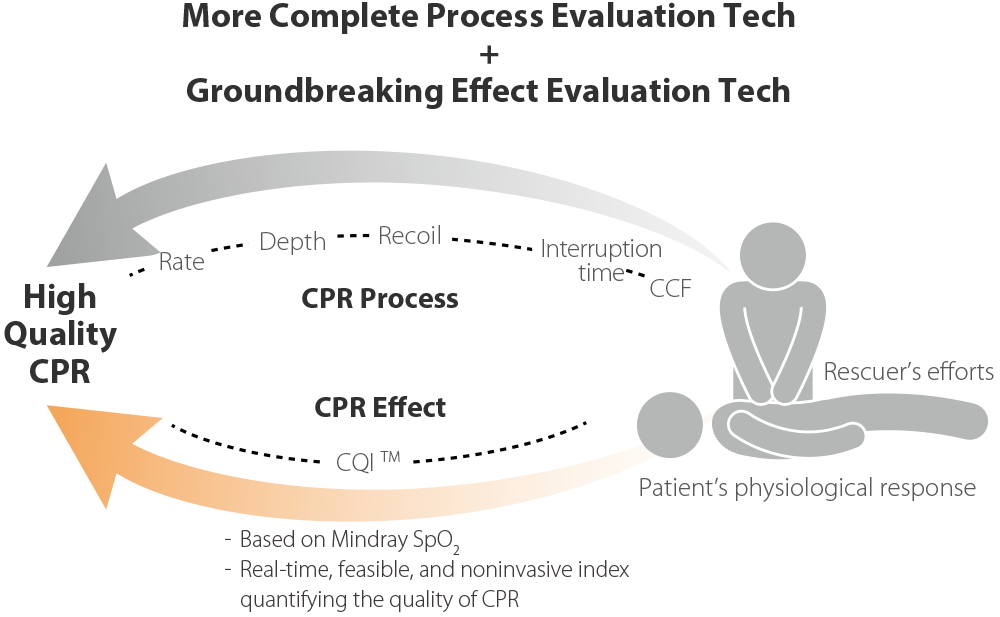

TriÃĄngulo de auxilio, mÃĄs completo

ReanimaciÃģn mÃĄs rÃĄpida